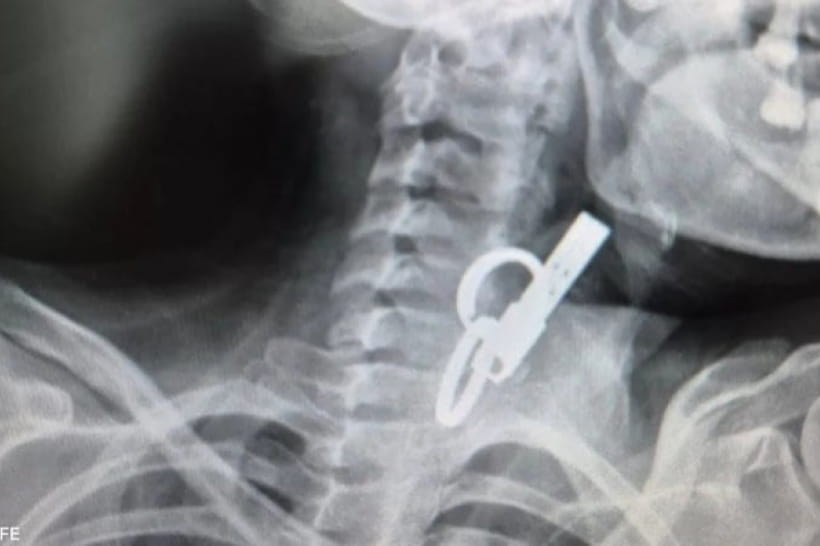

У селищі Гусятин, що на Тернопільщині, медики провели унікальну операцію з порятунку 40-річної жінки. Пацієнтка звернулася по допомогу в критичному стані, маючи в стравоході масивний сторонній предмет – ключ від дверей. Завдяки майстерності команди фахівців та сучасному обладнанню, жінку вдалося врятувати без традиційного хірургічного втручання, повідомляє "Дивогляд" із посиланням на КНП "Гусятинська КЛ" Гусятинської селищної ради.

Фото: КНП "Гусятинська КЛ" Гусятинської селищної ради

• Складність діагностики: спочатку медики побачили на екрані лише металеві кільця, і лише згодом зрозуміли, що мають справу з великим ключем.

• Ендоскопічний метод: замість складного хірургічного розрізу фахівці використали сучасний ендоскоп, обережно витягнувши предмет через ротову порожнину.

• Шанси на виживання: лікар підкреслив, що зазвичай пацієнти з такими тривалими термінами перебування сторонніх тіл у стравоході гинуть, тож цей випадок можна вважати справжнім медичним дивом.